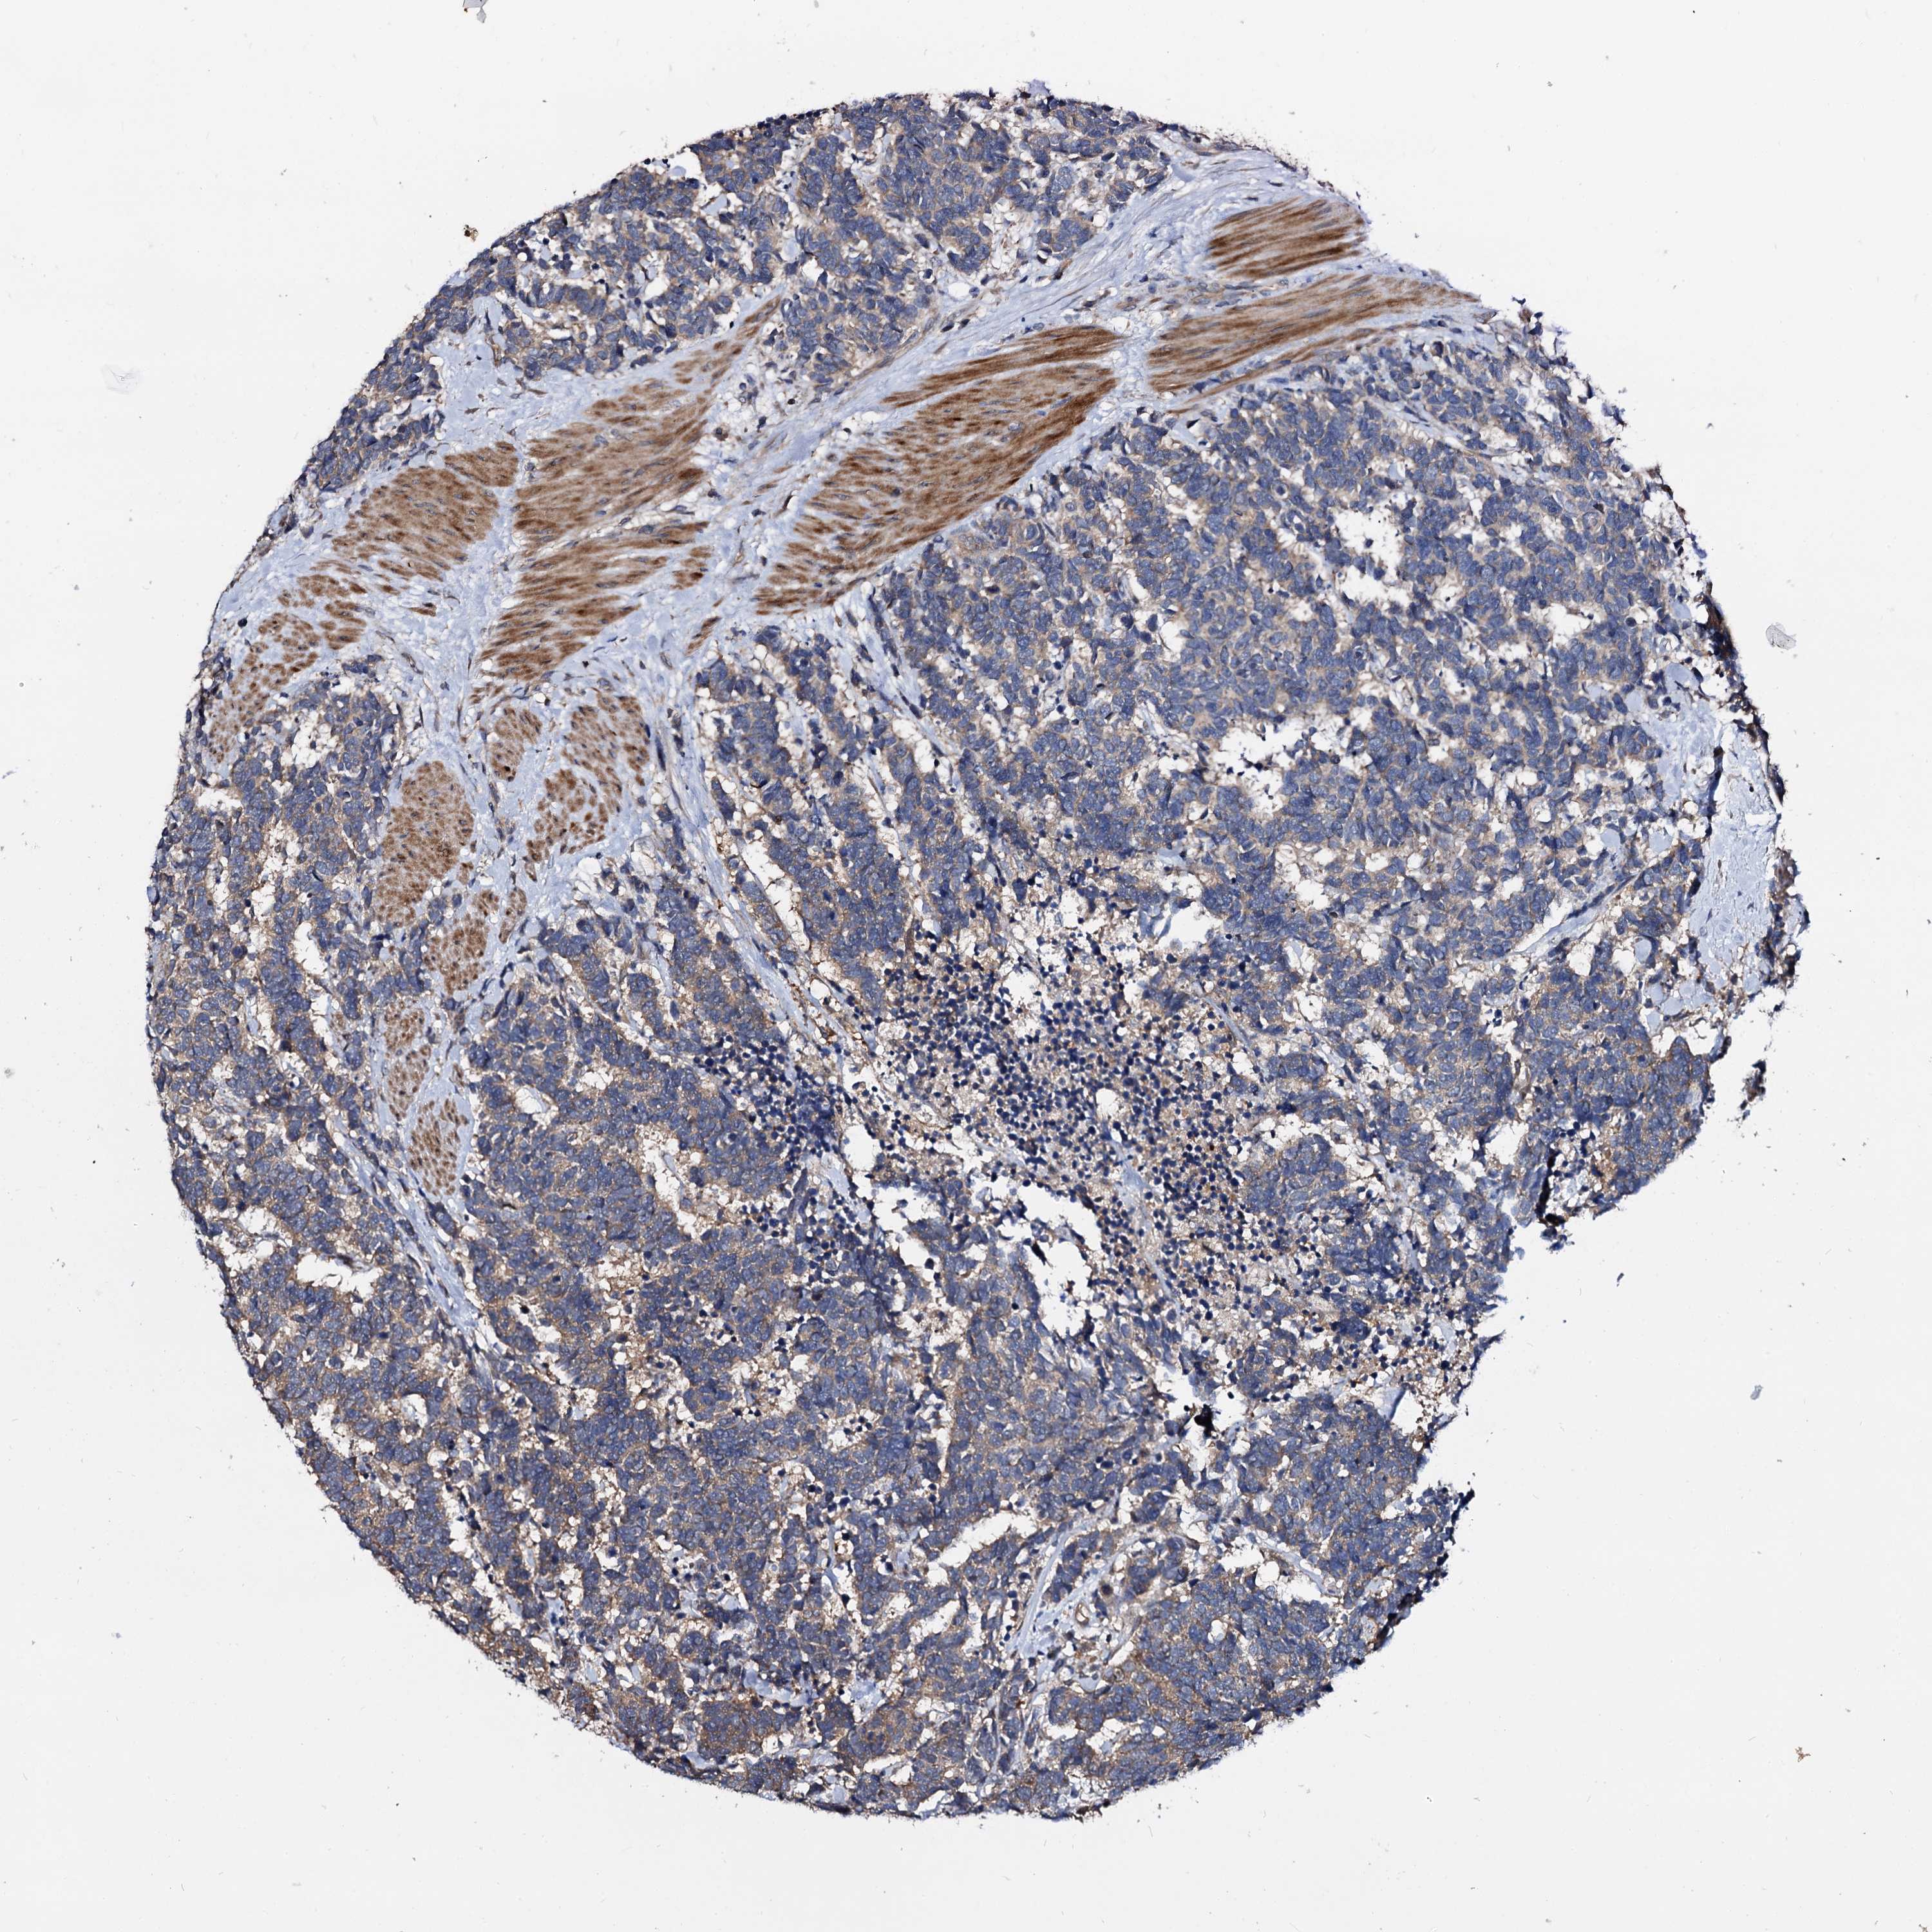

CARCINOID - Protein expressioni

A mouse-over function shows sample information and annotation data. Click on an image to view it in a full screen mode. Samples can be filtered based on level of antibody staining by selecting one or several of the following categories: high, medium, low and not detected. The assay and annotation is described here.

Antibody stainingi

Antibody staining in the annotated cell types in the current human tissue is reported as not detected, low, medium, or high, based on conventional immunohistochemistry profiling in selected tissues. This score is based on the combination of the staining intensity and fraction of stained cells.

Each image is clickable and will lead to virtual microscopy that enables deeper exploration of all samples and also displays staining intensity scores, fraction scores and subcellular localization as well as patient and tissue information for each sample.

Antibody HPA039392

Antibody HPA040503

Staining

High

Medium

Low

Not detected

Intensity

Strong

Moderate

Weak

Negative

Quantity

>75%

75%-25%

<25%

None

Location

Nuclear

Cytoplasmic/membranous

Cytoplasmic/membranous,nuclear

Carcinoid, malignant, NOS

Carcinoma, NOS